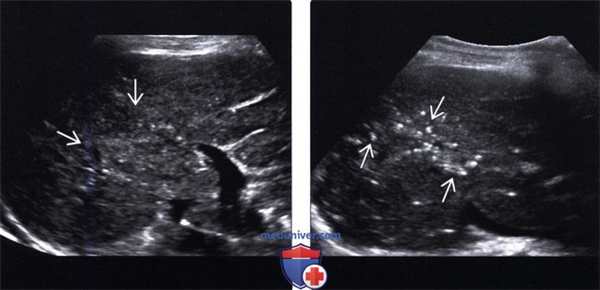

(Левый) Поперечный трансабдоминальный ультразвуковой срез. Отмечается неоднородность эхоструктуры паренхимы печени в виде пятен, вызванная диффузным распространением кандидозных микроабсцессов.

(Правый) Продольный ультразвуковой срез у того же пациента через два года после лечения диссеминированного кандидоза. Визуализируются множественные гиперэхогенные точечные кальфикаты в паренхиме, типичные для кандидозных микроабсцессов после лечения.